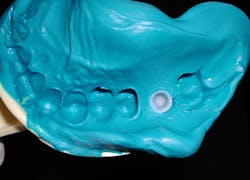

An abutment-level impression consists of placing a final stock restorative abutment that, once placed, is not removed from the implant. Abutment-level restorative components are designed with an antirotational feature (a flat plane) on the abutment (figure 1). A plastic impression coping is then snapped over the abutment, capturing the rotational orientation of the abutment in relation to adjacent teeth or other implants being restored (figure 2).When ordering abutment-level components, the practitioner determines the emergence diameter, gingival cuff height required based on the distance from the implant platform to the gingival margin of the sulcus, and the height of the abutment from the margin to the coronal height. The kit then contains the components that fit that particular abutment. The benefit of this type of system is that the implant surgeon can place the abutment at implant uncovery, so the restoring dentist does not need to manage healing abutment removal and restorative abutment placement. This can be beneficial to dentists who prefer not to be involved in this aspect of implant placement. Surgeons may consider this an added benefit for their referring dentists.

As the impression coping will be picked up in the impression, a stiffer impression material is recommended to ensure the coping is securely fixated in the impression upon removal. A heavy-body, tray, or putty vinyl polysiloxane (VPS) is recommended in the tray, and a light- or medium-body VPS can be injected intraorally around the gingival aspect before tray insertion. Use of a medium-body VPS in the tray will result in the coping being dislodged, which affects the accuracy of the impression. A stock tray is used for this technique.